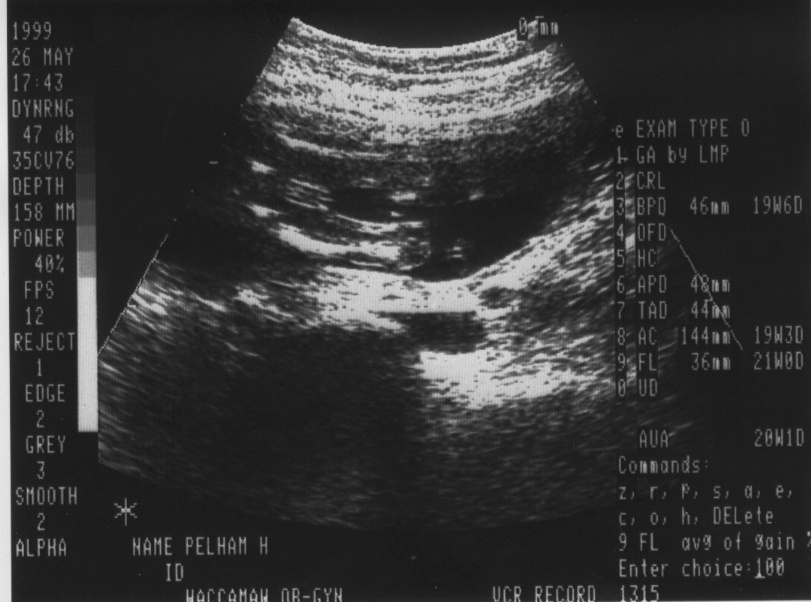

Which reminds me, George is, in fact, a he. This is a nearly

official announcement – our obstetrician wasn’t able to sex the baby because

he was sitting Indian style, but I had an ultrasound of my heart done a week

later, and the extremely accommodating ultrasound technician and I spent

most of the time spying on George. He wasn’t sitting Indian style that time,

and the pictures the technician printed for me are pretty explicit!

3/5/00 (H) Hey - we got to see International George's

heart beating during our latest ultrasound! It's going so fast, I'm

surprised it doesn't scare the cats when they sit in my lap.

Anyway, the child has been growing at a good clip, and our obstetrician says

he or she looks great, what little can be seen of him/her. (here's the

latest picture)

For those of you looking for the first baby picture, here it

is. Just click on it to see it bigger. The black dot in the center is the

child. I'm sure it is only the first picture of

many.